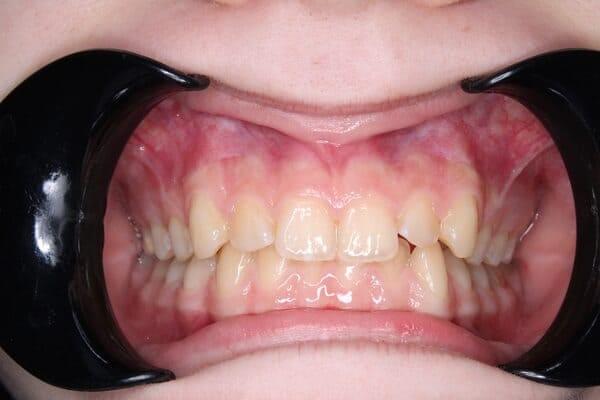

Видалення зубів мудрості – це важливий крок до гармонійної посмішки, особливо в підлітковому віці. Ми знаємо, що правильно обраний час для цієї процедури може запобігти багатьом проблемам в майбутньому.

вони можуть заважати лікуванню брекетами чи елайнерами, а в деяких випадках – звести нанівець його результат. Саме тому ортодонт часто рекомендує їх видалити до початку чи під час лікування.